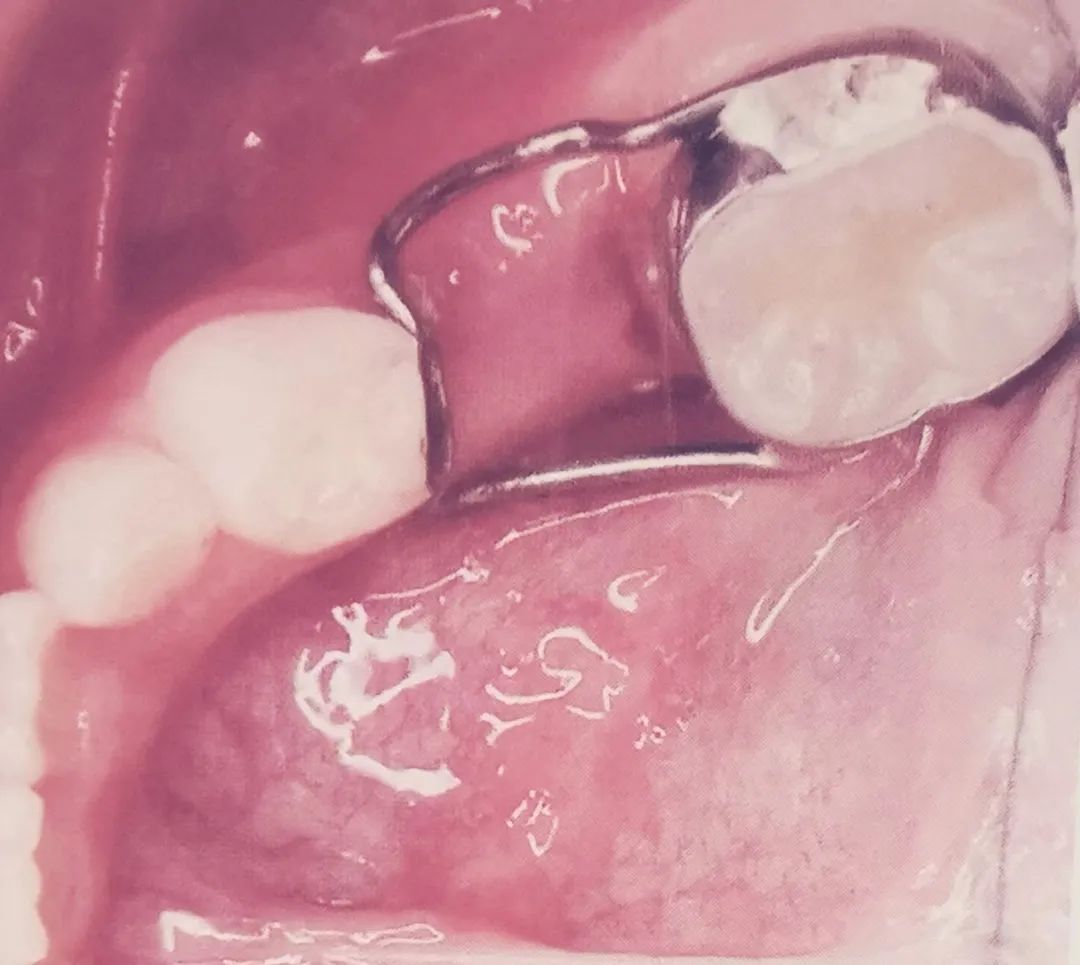

一般乳前牙早失,间隙变小或消失的可能性较小;乳尖牙及乳磨牙早失会导致间隙不同程度的丧失。为了防止邻牙向缺隙侧倾斜和对颌牙伸长,我们一般会通过全面检查,并结合X光片,根据患者的年龄、乳牙早失的数量、恒牙胚发育的程度以及邻牙的条件,明确采用哪种间隙保持器来保持早失牙的近远中距离和垂直向间隙,使继承恒牙能够正常萌出,防止牙列畸形的发生。在取模型制作保持器之前,需将邻牙龋坏牙或者已发生牙髓炎的邻牙治疗完全,以避免或减少中途因邻牙病变更换或去除间隙保持器情况。个别邻牙在佩戴保持器过程中发生龋坏或牙髓病变的,应遵医嘱及时就诊,由医生明确进一步诊治方案。大多数儿童都是有恒牙胚的,个别会有恒牙先天缺失,通过X牙片我们会明确恒牙有无及恒牙的发育情况。

很多家长十分担心孩子佩戴间隙保持器后会出现各种不适,会提出以上诸多疑问。人志明医生提示,首先间隙保持器上面没有假牙,它是一个支撑拔牙间隙的装置,一般试戴合适后用粘接固定在间隙前或者后面的邻牙上,不能天天摘戴,尽量避免咬过硬过难嚼碎的食物或者过粘的食物,以防脱落或者变形,平时要像刷牙一样刷干净。